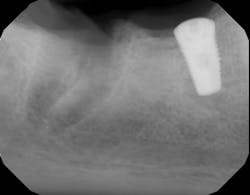

- The type of endodontic treatment dictates the length of healing. Nonsurgical endodontic treatment has a usual healing time of three months. Surgical intervention such as an apicoectomy due to large lesion size can take six to 12 months to heal (figures 1 and 2).